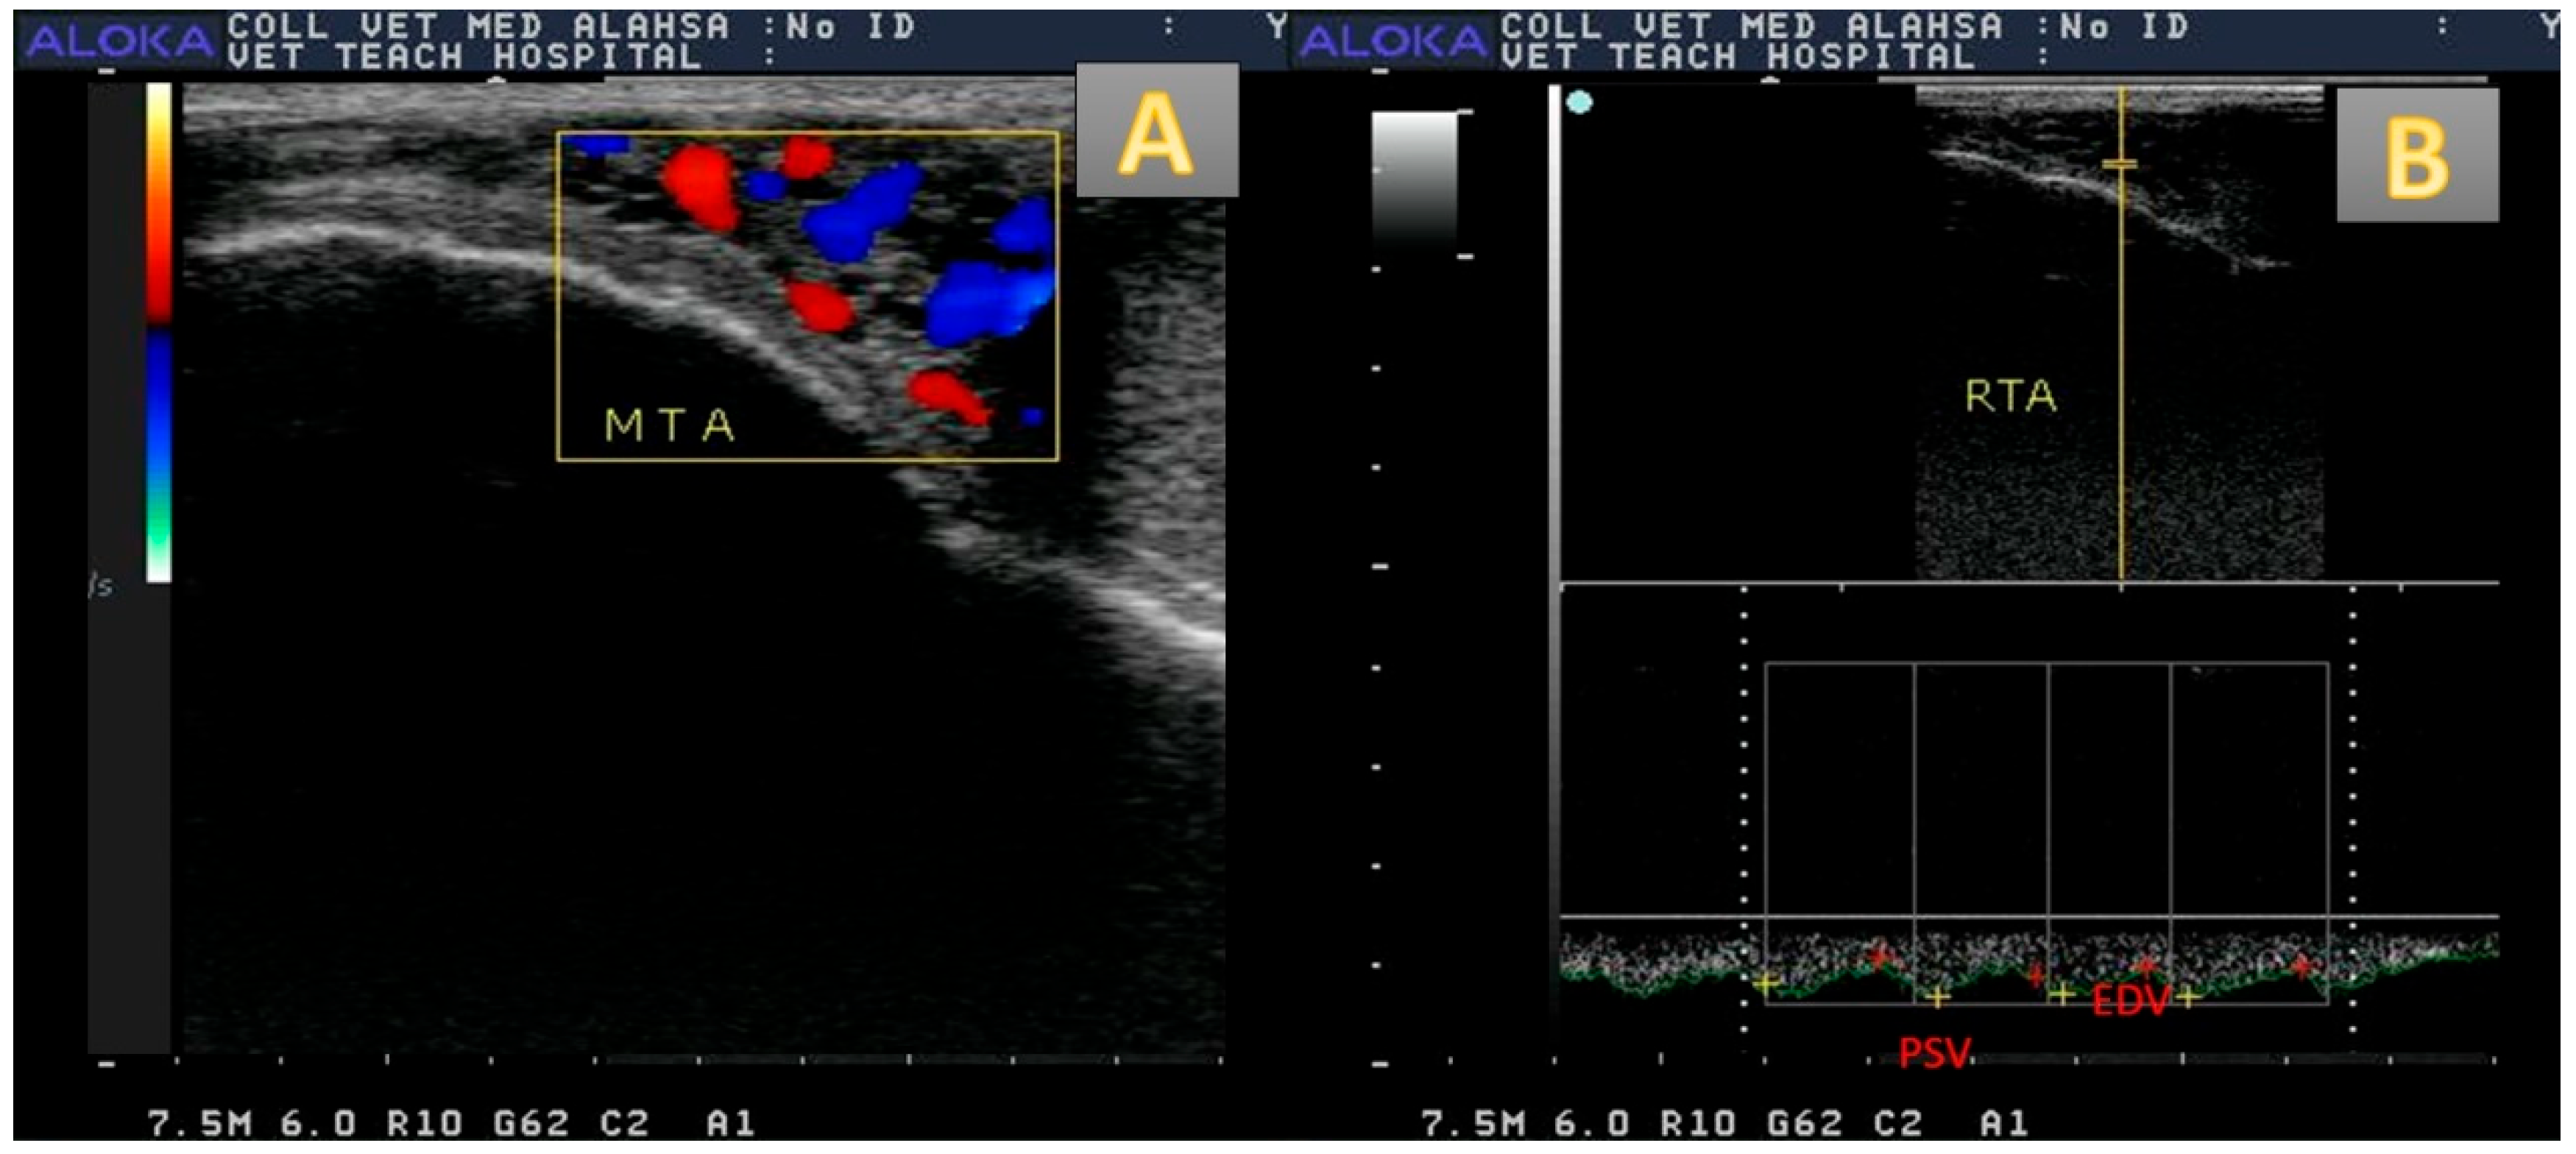

3.2. Testicular Vascularization

3.3. Testicular Morphometry and Echogenicity